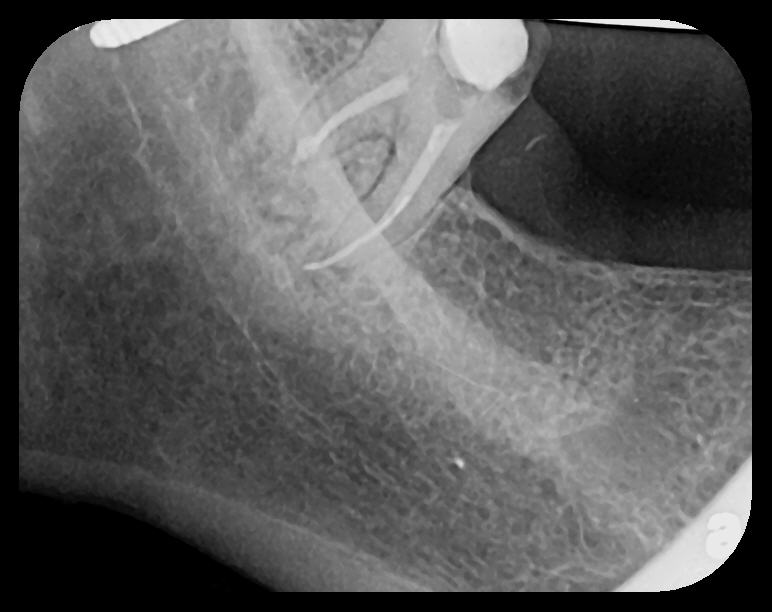

Fig 1. Left: Representative PSP BW radiograph with multiple restorative materials of varying radiographic densities. Tooth No. 31 demonstrates deep

caries on mesial aspect beneath the restorative. Radiolucency of carious lesion results from the low relative density of caries compared with healthy

tooth structure. Right: PSP BW radiograph optimized for view of multiple interproximal carious lesions.

Figure 1